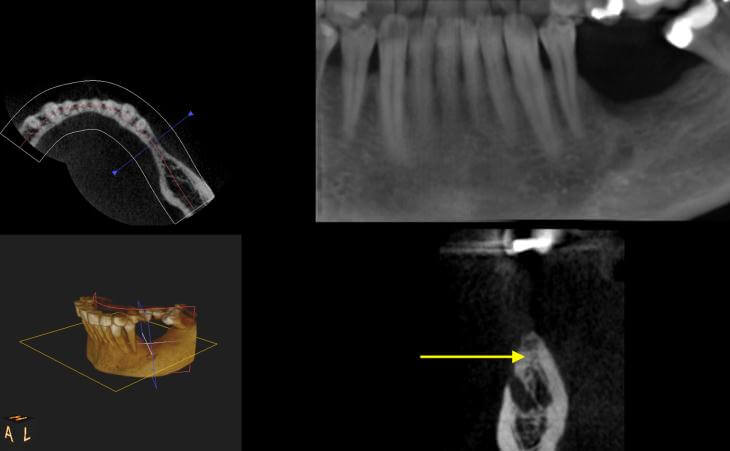

Patient has been missing lower left teeth for years. Developed large ridge defect from not having teeth. Pre surgical CT scan shows thin ridge with inadequate bone volume to place implants. Ridge bone graft was done. Special covering placed and secured. CT scan after 4 months of healing. Final post implant placement x-ray.